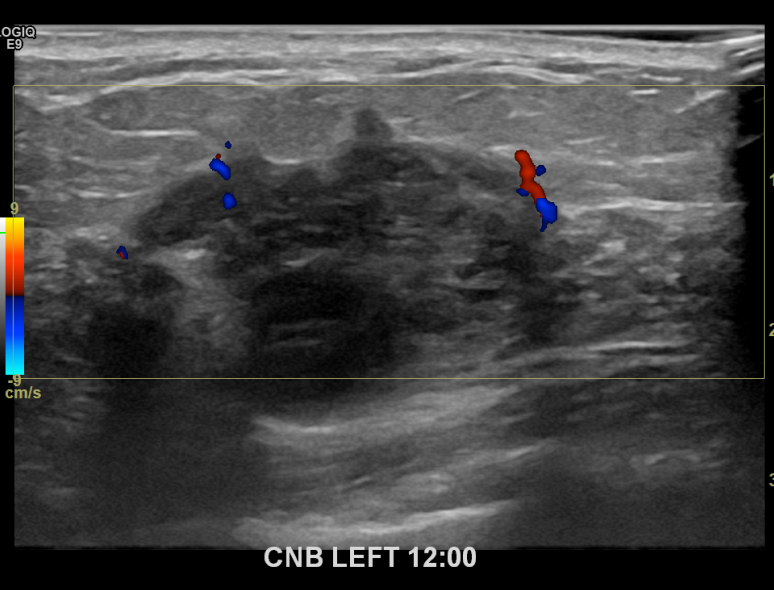

아산유외과개원후 676번째 유방암진단

상기환자 외부검사상 이상소견으로 내원하신 60대여성으로 좌측에 의심스러운혹 조직검사시행해 유방암 진단되었습니다.